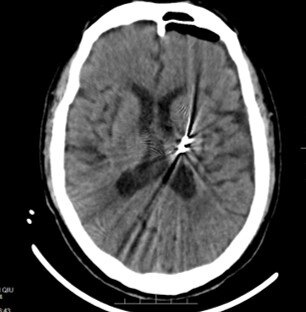

一日門診,一對夫婦帶著一個妙齡貌美的少女走進我的診室。????原來,經(jīng)人介紹,這對夫婦特意從家鄉(xiāng)趕來找我為他們寶貝女兒看病。我便請病人坐在我旁邊的椅子上問起病史來。????病人的母親說,她的女兒今年考進廣州的一所大學(xué),入學(xué)一個多月后的一天,她女兒突然感到咽喉痛、發(fā)熱、流涕等不適,于是便在校醫(yī)室就診,校醫(yī)室的醫(yī)生看后便下了一個“上呼吸道感染”的診斷,開了一些相應(yīng)的藥物給她服用,一周后咽喉痛和流涕癥狀消失了,但發(fā)熱仍存,同時還出現(xiàn)頭痛,這頭痛一旦出現(xiàn)便日漸加重,校醫(yī)室認為原來的病并沒有好,再加碼用上靜脈輸注抗生素治療,雖然發(fā)熱稍退,但頭痛確實越來越重,遠在家鄉(xiāng)的父母通過電話得知情況后,心疼女兒的他們便讓女兒從廣州回家治療調(diào)理,本意是等調(diào)理好了再回校上課。????讓他們?nèi)f萬沒有想到的是,女兒的病情以一種迅猛的速度在加重,頭痛越來越嚴(yán)重,用他們女兒的話說:頭就像要炸開一樣爆裂樣痛,難以忍受。與此同時還不時伴隨有惡心嘔吐等,他們感覺到女兒的病并不是“上呼吸道感染”這么簡單了,剛好有人告訴他我在診治頭痛方面很有辦法,于是便找上了。????面對主訴為頭痛的病人,或者癥狀中有明確頭痛的病人,我都是十分小心的,因為稍有不慎,就可能誤診或者漏診隱藏在頭痛這個癥狀背后的嚴(yán)重的疾病。能證明我對頭痛病人重視的“證據(jù)”之一就是無一例外地給他們看眼底。????是的,看眼底是很簡單的一項檢查,在診室就可以很快完成,但這必須會看、懂看,還有就是必須要不厭其煩地看,不抱僥幸心理地看??梢院敛豢鋸埖卣f,除了眼科醫(yī)生,其它科室的醫(yī)生已經(jīng)很多不會看眼底了,那些會看眼底的醫(yī)生已經(jīng)不習(xí)慣或者不耐煩給病人看眼底了。值得欣慰的是,我的研究生們都學(xué)會了看眼底,而且都會不厭其煩地給那些他們認為需要的病人看眼底。????我拿起眼底鏡準(zhǔn)備給她看眼底,這才發(fā)現(xiàn)這位姑娘的美麗。盡管被疾病折磨了這么長時間,但她的美依然自熱而然地展現(xiàn)在我的面前,這是一種天然的,無需雕飾的美。人們常說紅顏薄命,但我并不認可,薄命與否只是一個概率的問題,與美丑無關(guān)。?????????其實,在聽完病史后,我心中已經(jīng)隱約感到某種的不妙,可我還是希望我看到的眼底不是我心中想到的那種疾病的眼底改變。然而,事實總是很殘酷且血淋淋的:隨著我的眼底鏡的光線穿透她那美麗的眼睛的晶體進入眼底,典型的顱內(nèi)壓增高的眼底改變一覽無遺地展示在我的眼里,這樣的改變不可能是一個月內(nèi)可以完成的,我似乎看到那可怕恐怖的答案了!????為了盡快得到結(jié)果,我選擇了速度最快的一種檢查:頭顱CT平掃。約莫一個多小時后,給力的CT室的同事們便完成了所有該做的一切,病人的父母親看到報告后已經(jīng)明白了一切,于是便將病人留在候診室的長椅上休息,他們兩個進入我的診室。????盡管我有心理準(zhǔn)備,可當(dāng)我將CT片放在讀片燈前時,還是被眼前的影像嚇了一跳:一個巨大的腫瘤不偏不倚地生長在腦部的中央!再也沒有比這個結(jié)果更令人絕望的了,作為醫(yī)生的我深知,這樣的腫瘤,這樣的生長位置,我想,全世界沒有哪一位醫(yī)生敢動它一刀!????當(dāng)我把情況告訴這對可憐的父母時,當(dāng)他們明白將很快失去自己的寶貝女兒的時候,母親當(dāng)場失聲痛哭,貌似堅強的父親安慰著自己的妻子,可眼里分明已是滿眶的淚水了,于我而言,此時我任何勸慰的語言都是蒼白無力的,只有哀嘆疾病的無情,人類的無奈,醫(yī)生的愛莫能助了。????是啊,作為醫(yī)生能夠做的并不多,他們偶爾才能去治愈,常常去幫助,卻總是去安慰。